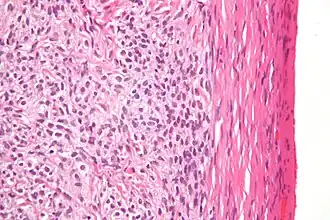

Fort grossissement d'un thécome, coloration à l'hématoxyline et à l'éosine.

Au microscope, les cellules tumorales ont un cytoplasme abondant rempli de lipides.